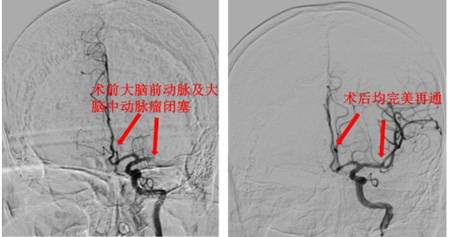

病例1——双血管栓塞的“一网打尽”:(60岁男性)因突发意识障碍紧急来院。神经内科立即启动静脉溶栓,患者意识稍好转但仍模糊。脑卒中一站式检查揭示病因复杂:左侧大脑中动脉M1段合并大脑前动脉A2段均发生闭塞。与家属充分沟通后,神经外科介入团队紧急施治,凭借精准技术一次性成功取出两处栓子,术后患者恢复良好。